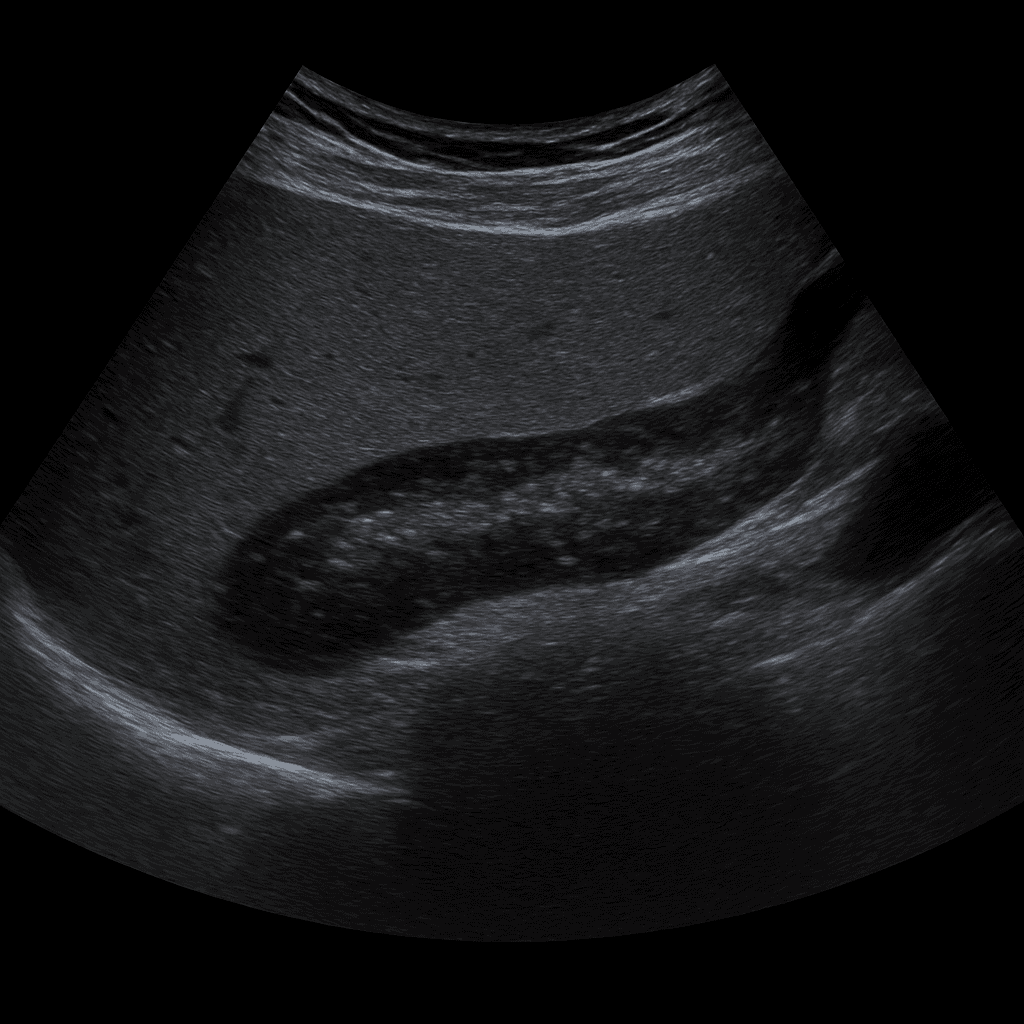

En ultraljudsundersökning av pancreas eller (bukspottkörteln) används för att undersöka körtelns storlek, form, vävnadsstruktur och omgivande organ. Undersökningen utförs av specialistläkare inom radiologi och ger bilder i realtid som kan visa förändringar orsakade av inflammation, cystor, stenar eller tumörer. Ultraljud pancreas används ofta som första steg vid utredning av buksmärta, gulsot eller avvikande lever- och bukspottkörtelvärden i blodprover.

Till skillnad från MR och DT, som används för mer detaljerad kartläggning av körtelvävnad och gångsystem, är ultraljud en snabb och strålningsfri metod för att upptäcka större strukturella förändringar, vätskeansamlingar och omgivande inflammation. Ultraljud kan ibland vara begränsat vid gasfyllda tarmar eller djup bukvävnad, men fungerar utmärkt som initial undersökning och vid uppföljning av kända fynd.

Undersökningen utförs medan du ligger på rygg eller vänster sida. En gel appliceras på huden och läkaren för ultraljudsproben över den övre delen av buken, oftast under vänster revbensbåge. Undersökningen tar vanligtvis 15–20 minuter. För bästa bildkvalitet rekommenderas att du fastar i cirka 4–6 timmar innan undersökningen för att minska mängden luft i magsäcken och tarmen.